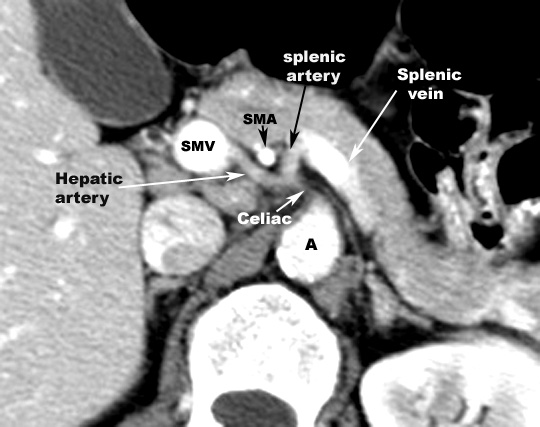

- Relationship:

- Head

- Posterior

- SMV

- Splenic vein

- IVC

- Terminal portion of renal vein

- Right crus of diaphragm

- Anterior

- Transverse colon

- Uncinate process passes in front

of Aorta

- Lateral

- Neck

- Beginning of portal vein

- Body

- Stomach separated by omental bursa

- Aorta

- SMA

- Left crus of diaphragm

- Left adrenal

- Left kidney

- Left renal vein

- Inferior

- Transverse mesocolon

- Duodeno-jejunal junction

- Left colic flexure

- Superior border